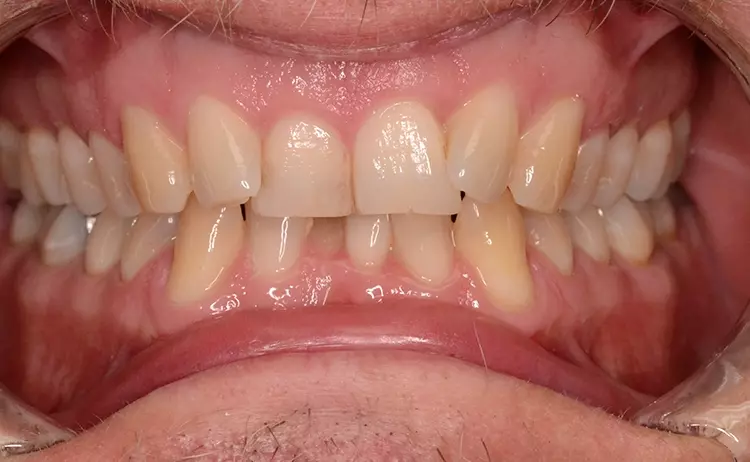

Neugestaltung der Front bei starken Zahnfehlstellungen

Bei dem heute 49-jährigen Patienten wurde seit Kindertagen versäumt, die Ober- und Unterkieferzahnbögen kieferorthopädisch auszurichten. Der Patient leidet seitdem stark unter seinen Zahnfehlstellungen.

Die Fraktur des stark elongierten Zahnes 21 war für den Patienten der Ausgangspunkt, sowohl die Front des Ober- als auch des Unterkiefers prothetisch überarbeiten zu lassen. Dabei wurde der frakturierte Zahn 21 durch ein navigiert eingesetztes Sofortimplantat ersetzt, während die verschachtelt stehenden Zähne 12 und 42 durch eine Brückenversorgung korrigiert wurden (Abb. 4a-j).